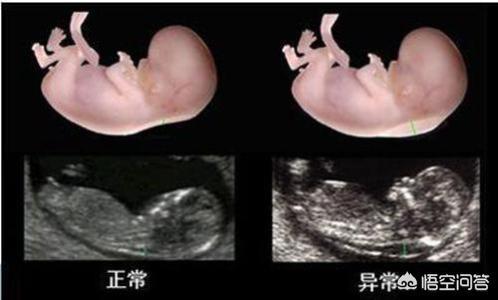

B超和D超(彩超)的区别是

D超(彩超)是在黑白B超基础上发展起来的,除了具有比B超高清的分辨率,又同时提供了受检部位血流动力学的丰富信息,彩超可以检查的范围更广,细节方面也更加详细。彩超可以看清组织内部的形态、大小、以及内部的结构,另外还能看到内部血液流动的情况,观察到病变内部有无血管的分布。

B超和彩超对受检部位的显示均为黑白色,彩超增加红蓝色血流信息显示项目。